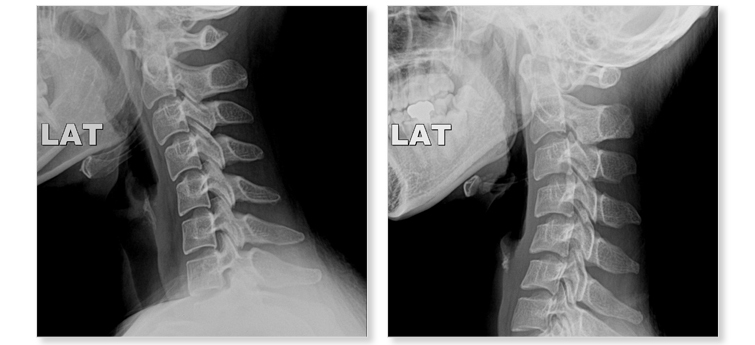

목디스크란 목뼈 사이에 있는 디스크가 손상되어 신경을 압박하는 질환을 의미합니다. 디스크는 젤리와 같은 수핵과 섬유륜으로 구성되어 있습니다. 섬유륜이 손상되면 수핵이 밖으로 밀려나와 신경을 압박하게 됩니다.

목디스크는 주로 잘못된 자세, 과도한 스트레스, 외상 등으로 발생합니다. 잘못된 자세로 장시간 컴퓨터를 사용하거나 운전을 하면 목에 무리가 가고 디스크가 손상될 수 있습니다.

또한 과도한 스트레스는 근육을 긴장시켜 디스크에 손상을 줄 수 있습니다. 외상은 교통사고, 운동 중 충격 등으로 목뼈가 부러지거나 골절되면 디스크가 손상될 수 있습니다.